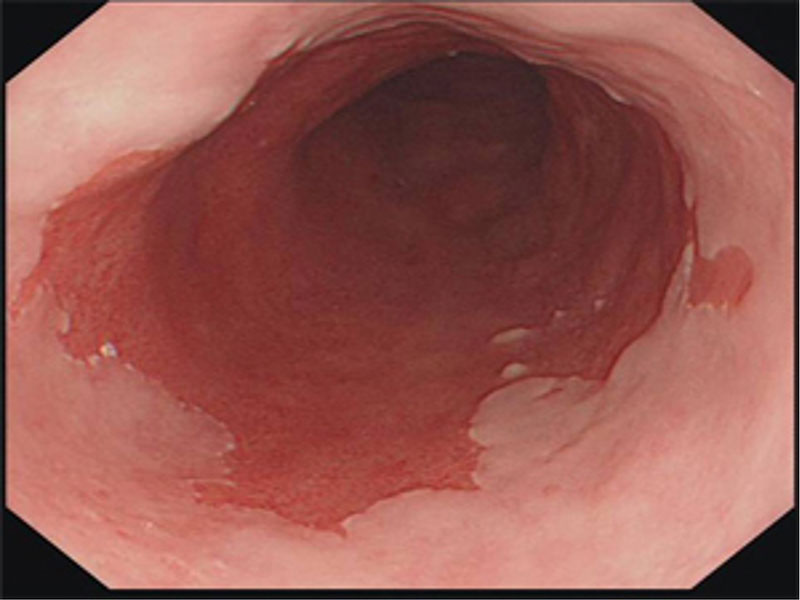

Endoskopide Reflü ile İlgili Ne Görülür?

Reflünün sindirim sisteminde yarattığı hasarı görmenin en kesin yolu endoskopidir. Yemek borusuna kaçan asit hasar yarattıysa bunu görebiliriz.

Yüksek çözünürlük (HD) en yeni kuşak cihazlarda mevcuttur. Dokuları daha iyi görmeyi ve ayrıntıları yakalamayı sağlar. Narrow Band Imaging (NBI) ise normal ışık dalga boylarını değiştirerek görüntü elde etmeyi sağlar; NBI ile daha derinlemesine görüntü elde edilir.